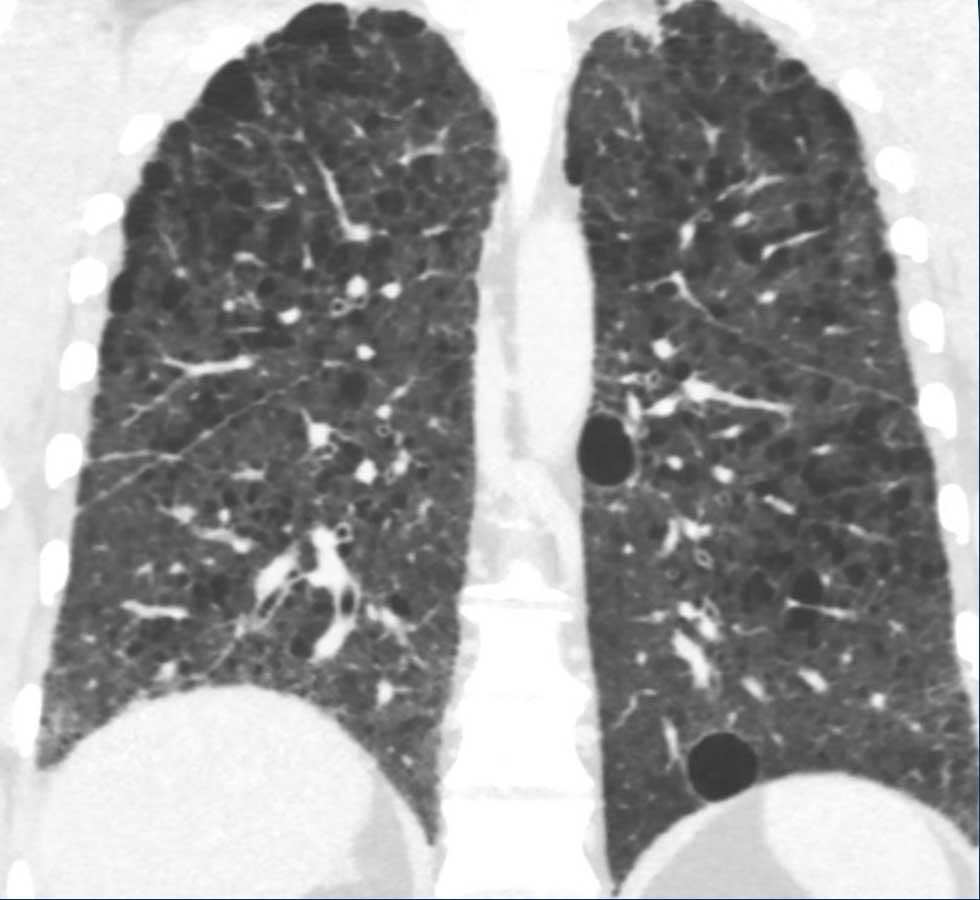

LAM biểu hiện với số lượng lớn các nang hình tròn, bờ đều đặn, phân bố rải rác khắp nhu mô phổi.

- Nhiều nang ở một phụ nữ trẻ. Lưu ý hình dạng tròn đều và phân bố lan tỏa.

- Trường hợp LAM nặng. Khi có tiền sử hút thuốc lá, chẩn đoán phân biệt cần đặt ra là LCH (giai đoạn tiến triển).

- Phân bố lan tỏa trong LAM.

Các hình ảnh này thuộc về một phụ nữ 39 tuổi với triệu chứng khó thở.

Chẩn đoán có khả năng nhất là gì?

Nhận xét hình ảnh

Có nhiều nang thành mỏng.

Lưu ý các nang phân bố đều khắp hai phổi.

Các ngách màng phổi cũng bị tổn thương (mũi tên).

Điều này cho phép loại trừ chẩn đoán LCH.

Chẩn đoán có khả năng nhất là LAM.